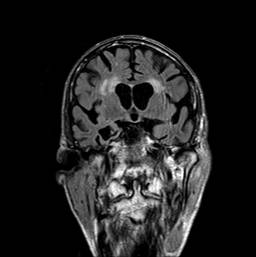

Hjerne, aldersdegeneration, MR

MR optagelse af aldersforandringer i hjernen ud for ventriklerne samt generel atrofi af storhjernen.